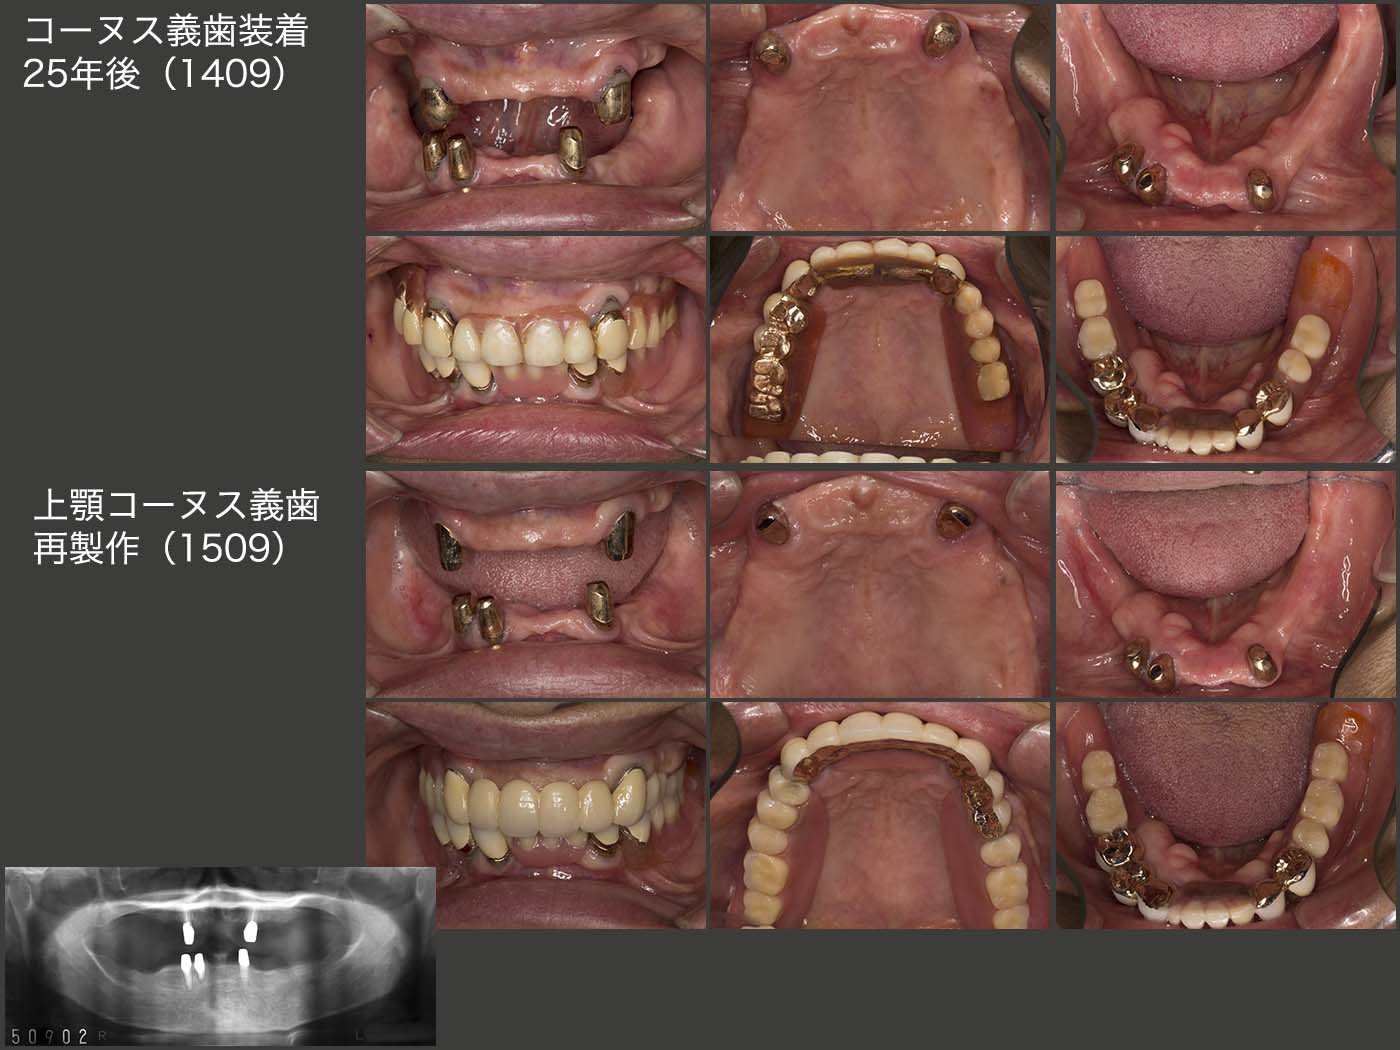

上段のスライドは,コーヌス義歯装着後25年経過した2014年9月の状態.初診終了時上顎は6本,下顎は7本歯が残っていたが,14年には上顎は2本,下顎は3本と,この25年の間に合計8本の歯を失った.しかし,上下顎のコーヌス義歯は25年経過してもなお使用することができた.このように,将来に変化に対応できることがコーヌス義歯の利点の一つである.

しかし,15年9月,上顎左右犬歯のマージン部の2次カリエスが大きくなり,また内外冠の維持力の低下がみられたため,上顎義歯を再製作せざるを得なかった.下顎は,上顎の新義歯に合わせて人工歯を交換したりしているが,昔のままの義歯を使用し続けている.

2016年2月に左上3,17年5月に右上3それぞれの内冠が立て続きにコアごと脱離した.15年の内外冠再製作の際,前のままのコアを使用したが,う蝕がコアの内部にまで侵食していたのかもしれない.何度か内冠を再合着したが,19年9月,OPAアタッチメントに変更した.外冠がそのまま再利用でき,根面アタッチメントの周囲を開放できることから,コーヌス冠のリカバリーによく利用している.

また,19年9月の時点で,下顎の残存歯が風前の灯火の状態であった.下顎の総義歯の維持安定は相当難しいことから,いつ総義歯になっても構わないように,11月に2本のインプラントを埋入した.20年7月,まだ下顎残存歯は使用可能とのこと.インプラントの出番はまだない.